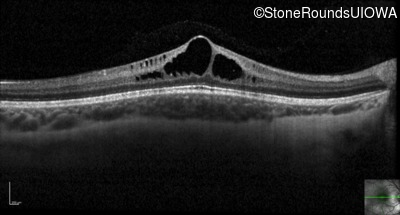

Optical Coherence Tomography - Left - 20/60 sc

Exemplar / OCT Stack